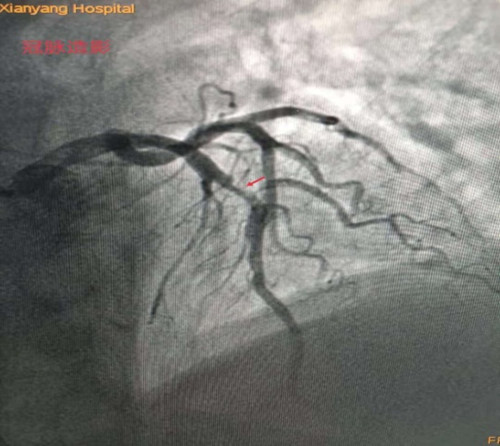

李新國主任為蒿大叔做了急診冠脈造影檢查,提示前降支近中段90%狹窄, D1開口99%狹窄,可見血栓影,結(jié)合術(shù)前心臟超聲檢查發(fā)現(xiàn)患者心臟腱索水平以下左室前間壁、前壁、前側(cè)壁運動搏幅減低,梗死范圍大,考慮罪犯血管為前降支近中段,在前降支近中段植入了一枚支架,開通閉塞血管。經(jīng)過1個多小時的搶救,蒿大叔總算從鬼門關(guān)被救了回來了。